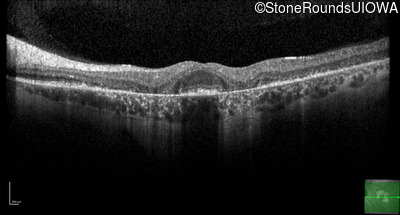

Optical Coherence Tomography - Right - 20/32 +2

Exemplar / OCT Stack